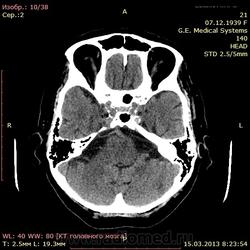

А как по мне, то тут геморрагический инсульт. Есть дислокация срединных структур слева.

Геморрагический инфаркт левой височной доли (в проекции таламуса слева) как правильно по локализации сам не знаю, скорее все таки таламус, со смещением срединных структур вправо, третий и левый боковой желудочек частично компримированы, формируется зона перифокального отека

тут либо геморрагический инсульт с перифокальным отеком, либо ишемический инсульт с геморагическим пропитыванием. Как их различить? Что скажут опытные коллеги?

Типичное медиальное кровоизлияние (в таламусе, медиальнее внутренней капсулы), уже не совсем свежее, плотность уже более низкая и зона отека приличная.

КТ признаки кровоизлияния в базальных ядрах, отделах с выраженными признаками перифирического отека. Про давность - сами пусть спросят , но скорее не свежак, до 5-6 дней.

Описывайте как геморрагический инсульт с объемным действием (смещением) на срединные структуры мозга. Померяйте плотности для оценки стадии. А различить на КТ две обговариваемые формы думаю нельзя. Разве что при пропитывании не будет такой четкой динамики изменения плотности очага. В литературе не встречал.